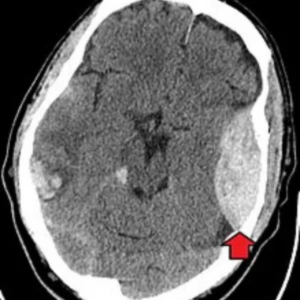

শিশুদের ক্যান্সার